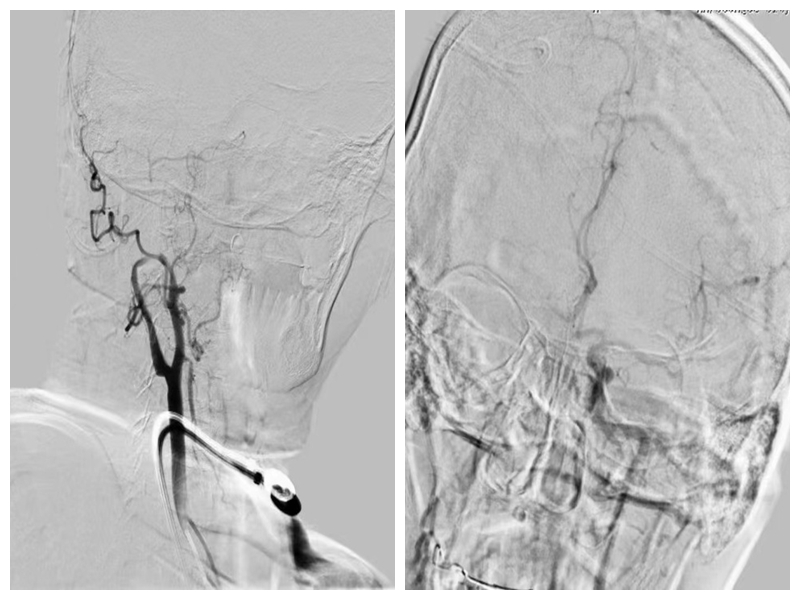

术前造影

血管内介入取栓术在国际上已被公认为急性脑梗死超早期治疗的重要技术。取栓时,医生采用微导管技术,将取栓装置从患者的下肢动脉送到病变的颅内动脉处,然后用取栓装置 “抓捕”堵住血管的血栓,迅速恢复血管通畅,血管再通率可以达到72%-100%。